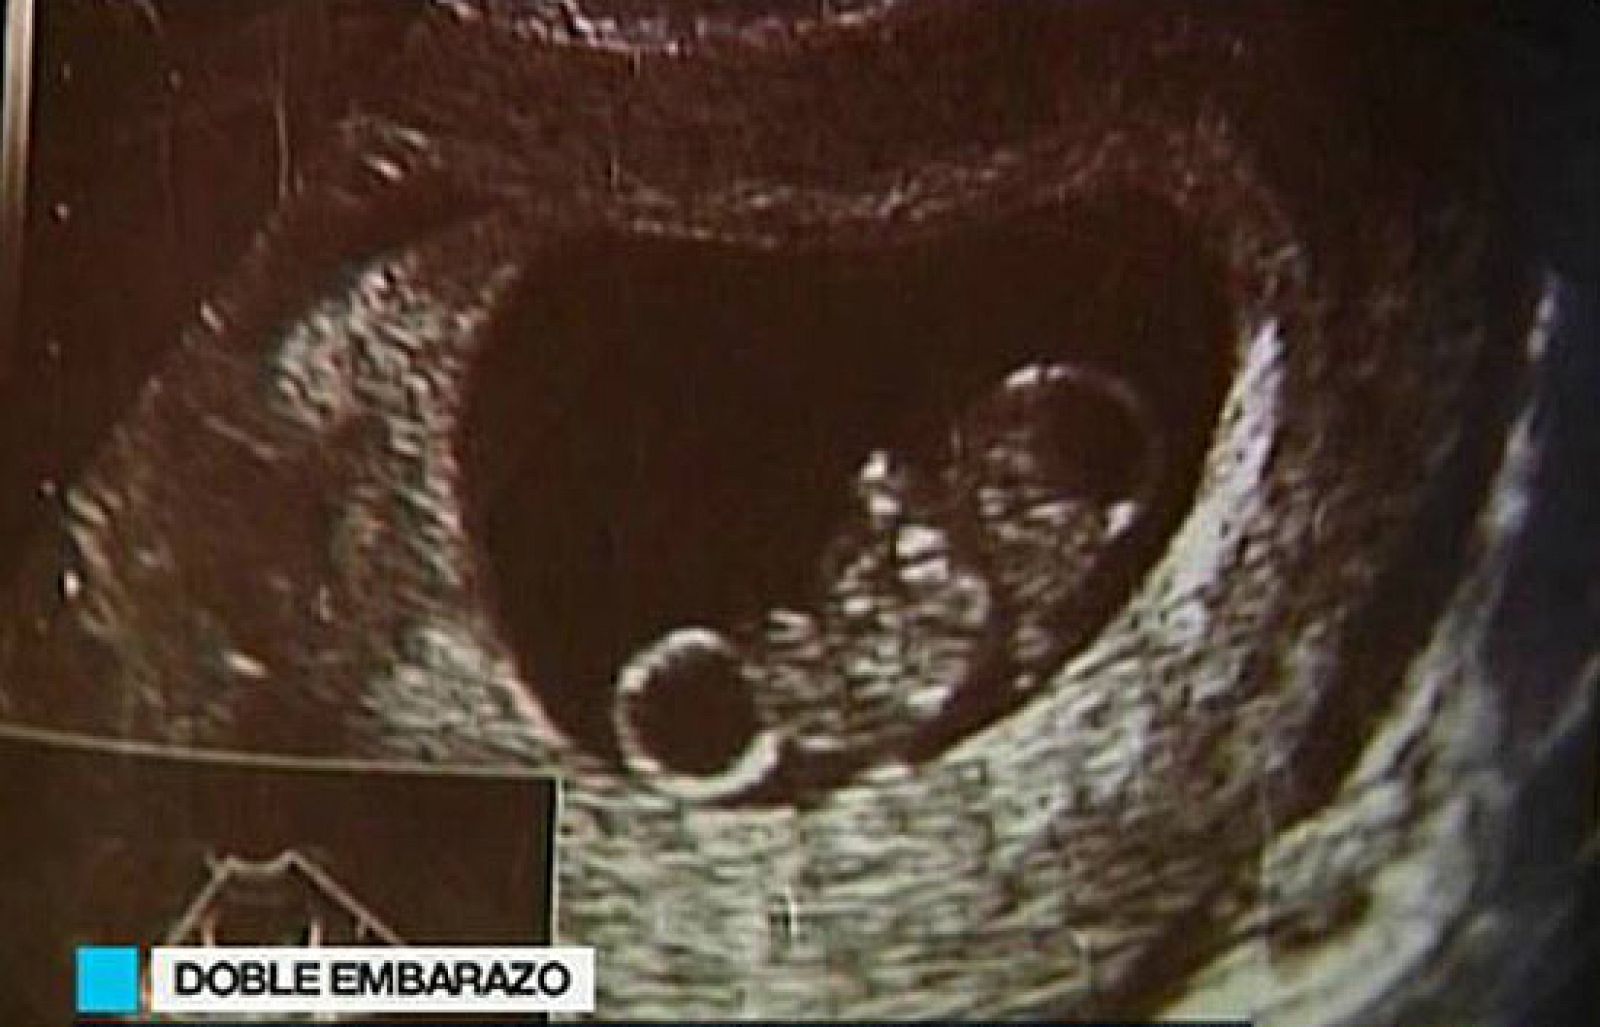

Se queda embarazada estando embarazada